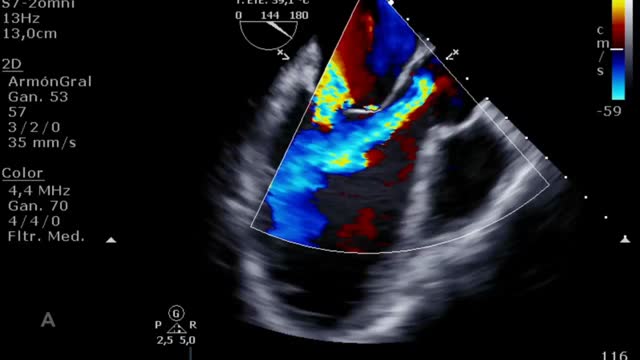

El aumento de la poscarga que condiciona la ECMO, junto con la baja contractilidad ventricular izquierda, puede comprometer la apertura valvular aórtica, pudiendo presentar un cierre precoz de la válvula (suplementario 13) e incluso permanecer cerrada (fig. 3 y suplementario 14).

Por último, muchos de los pacientes con ECMO VA pueden tener algún otro dispositivo de asistencia ventricular izquierda (BCIAo, Impella®) como medida de descarga ventricular34 y de los que también deberemos controlar su posición y funcionamiento12. En el caso del BCIAo, mediante ETT/ETE podremos observar el inflado del balón a nivel de la aorta descendente con su extremo distal a nivel del nacimiento de la subclavia izquierda (suplementario 17). El Impella® se puede explorar tanto por ETT (paraesternal de eje largo o apical de 3 cámaras) como por ETE (mediesofágico 120°) y debemos observar el dispositivo entrando desde la aorta ascendente y el inlet o zona de succión a 3-4cm de la válvula aórtica35,36 (fig. 4 y suplementario 18).